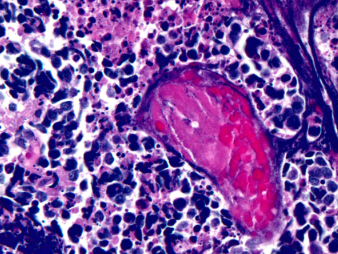

Px con pérdida de peso, dolor torácico y disnea. Observas este fenómeno histológico y alteración RB, P53, MYC.

pincelada de azzopardi ~ Ca.P.Micro